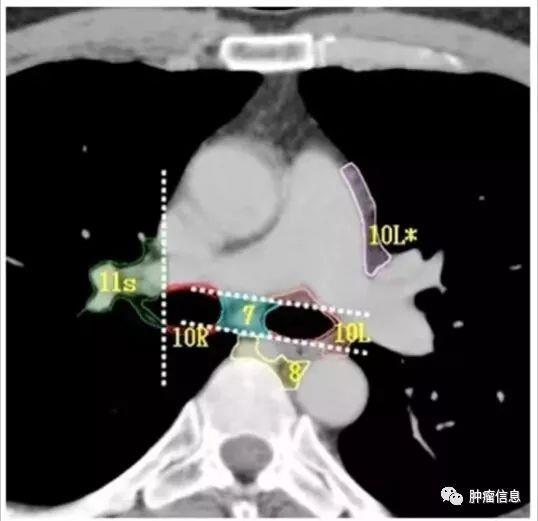

第10组淋巴结

与主支气管和肺门血管相邻的淋巴结上界:右侧奇静脉下缘,在左侧是肺动静脉的上缘。下界:双侧叶间区域

第11组淋巴结

第11组即肺叶间淋巴结,位于支气管分叉处。左侧第11组淋巴结位于第二隆突的下方。右侧的第11组淋巴结又区分为11s(右侧上叶支气管和中间支气管之间)和11i(右侧中叶支气管和下叶支气管之间)。